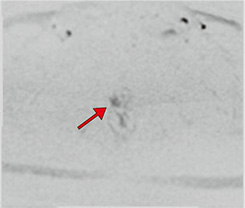

Aplio meによる臨床画像 症例:前立腺がんに対する経直腸エコーによる針生検

d:cと合致した部位にADCにてPI-RADS 4病変を認める。cの部位とbの画像でSMI陽性の病変は一致している。 d:cと合致した部位にADCにてPI-RADS 4病変を認める。

cの部位とbの画像でSMI陽性の病変は一致している。

abcd図

クリニックでは、通常の検査のほか前立腺針生検でもSMIを活用している。SMIは、モーションアーチファクトを除去するアルゴリズムを使用し、従来のカラードプラでは描出困難だった微細血管の低流速血流を高感度に描出できる。前立腺針生検は事前にMRI検査を行い、MR画像を参考に会陰部から針を挿入し組織を採取するが、SMIで前立腺がん特有の微細な血流の有無を確認しながら行うため、通常の前立腺針生検より高精度に検査が行える。宮嶋院長は、「MRI所見でPI-RADS(Prostate Imaging Reporting and DataSystem)スコアが4以上であれば、SMIで微小血管血流が検出できる印象です。実際に、SMIによりMRI所見と同様に血流が描出され、腫瘍を検出できた症例もあり、大変有用だと思います」と評価する。